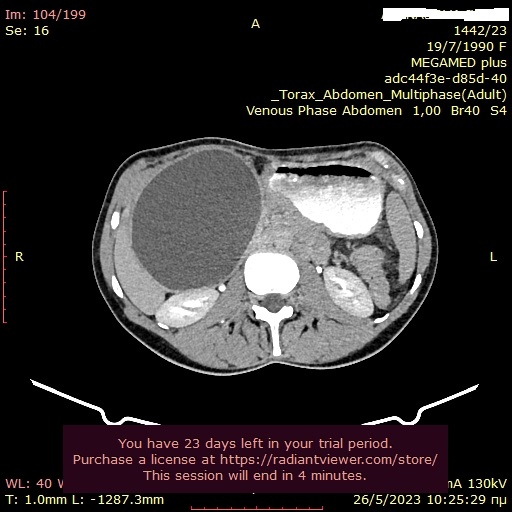

Άνδρας 43 ετών, χωρίς προηγούμενο ατομικό ή οικογενειακό ιστορικό, εμφάνισε επίμονους εμέτους και επιγαστραλγία. Υποβλήθηκε σε αξονική τομογραφία θώρακος, άνω και κάτω κοιλίας από το θεράποντα ιατρό του που έδειξε διάχυτη θωρακική και κοιλιακή λεμφαδενοπάθεια, με διογκωμένους λεμφαδένες στον υποτροπιδικό χώρο, στον αλλήρειο τρίποδα, στον ηπατοδωδεκαδακτυλικό σύνδεσμο και πέριξ του παγκρέατος. Ο ασθενής παραπέμφθηκε για ενδοσκοπικό υπέρηχο και λήψη βιοψιών από τους λεμφαδένες. Έγινε βιοψία με ειδική βελόνα για λήψη ιστοτεμαχίων (Pro-Core 19g) από λεμφαδένες σε 3 διαφορετικές θέσεις (υποτροπιδικά, αλληρείου τρίποδα και ηπατοδωδεκαδακτυλικού συνδέσμου). Η ιστολογική εξέταση και ο ανοσοϊστοχημικός έλεγχος έδειξε αδενοκαρκίνωμα χαμηλής διαφοροποίησης χωρίς θετικότητα στις επιμέρους, ειδικές χρώσεις. Ο ενδοσκοπικός έλεγχος του πεπτικού επιβεβαίωσε την ύπαρξη νεο-εξεργασίας στην ηπατική καμπή του παχέος εντέρου που ιστολογικά ήταν ένα αδενοκαρκίνωμα χαμηλής διαφοροποίησης. Ο ασθενής παραπέμφθηκε για προεγχειρητική χημειοθεραπεία και χειρουργική αντιμετώπιση.

CT: υποτροπιδικός λεμφαδένας

CT: λεμφαδένας αλληρείου τρίποδα

CT: λεμφαδένας ηπατοδωδεκαδακτυλικού συνδέσμουνδεσμο